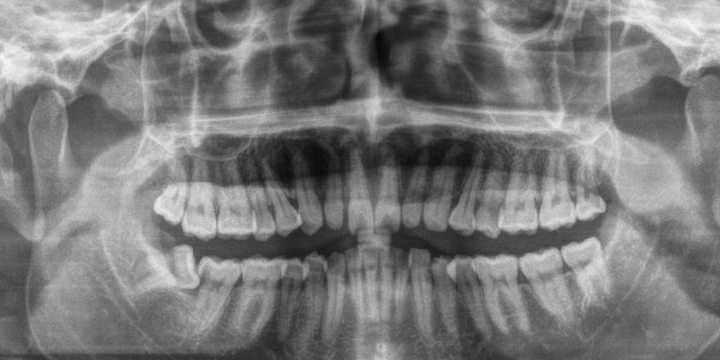

矫正前-------在做矫正前,需要先面诊,拍片子,出方案,收费如下:

面诊费用+一次性检查材料费用+拍x光片费用+口扫费用(或者取模型)+出方案费用。